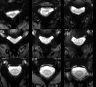

QC: Functional Reference Montage

What to look for:

- ✅ Clear definition of spinal cord against CSF (bright CSF, dark cord in T2*-weighted).

- ✅ No severe blurring (indicates robust reference construction worked).

- ❌ FAIL: "Ghosting" or double-images of the cord.